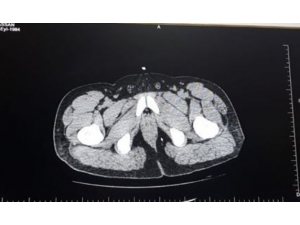

İki Yabancı Uyruklu Yolcunun Mide Ve Bağırsaklarında Uyuşturucu Taşıdıkları Ortaya Çıktı